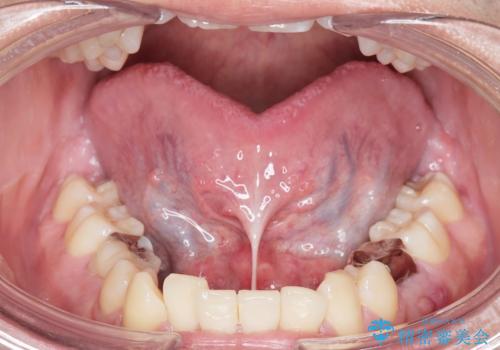

Dr. 長嶋美咲の症例写真